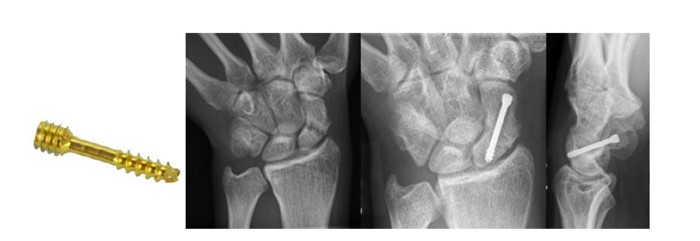

Оперативное лечение. Основная цель хирургического вмешательства – стабилизация перелома ладьевидной кости и быстрое восстановление кровоснабжения. Во время операции устраняется смещение костных фрагментов и выполняется их фиксация. В большинстве случаев применяется компрессирующий винт Герберта.

Использование винта Герберта для стабилизации отломков ладьевидной кости

Современные винты для ладьевидной кости имеют на концах разнонаправленную резьбу, что позволяет создать компрессию между костными фрагментами. Также могут использоваться костные трансплантаты как самостоятельный метод фиксации или в сочетании с винтом Герберта. Разрез может быть выполнен на ладонной или тыльной стороне запястья. Свежие переломы фиксируются винтом через разрез размером 3–5 мм с рентген-контролем.